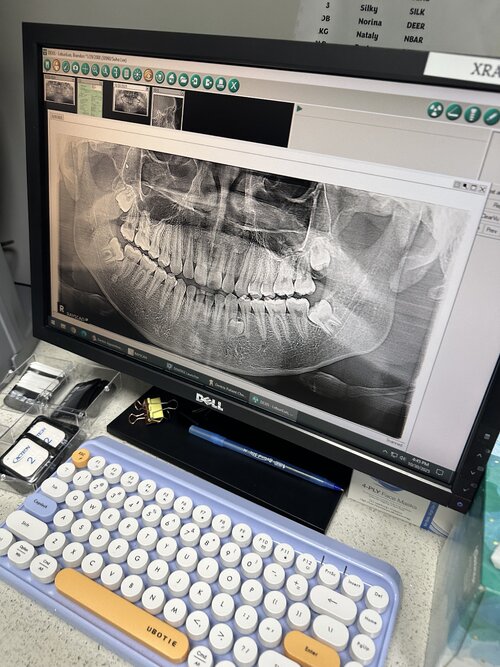

Im currently 18 yr old asian male, I have an underbite, and below I’ve attached images of some of the x-rays taken. My orthodontic surgeon is suggesting to pull teeth, but I know that’s utter nonsense and will recess me like crazy. I tried to bring up the possibility of a maxillary deficiency rather than a mandibular one, but he argued that my lower jaw was protruding and that my maxilla was fine. He said moving my upper jaw forward would give me an unnatural look, which I don’t really believe all that much. May the good people of org advise me on my situation? I’m thinking I should just save up for lefort later on. I also have all my wisdom teeth still even though I should probably get them extracted (at least the bottom ones). Would getting my wisdom teeth extracted help my underbite?